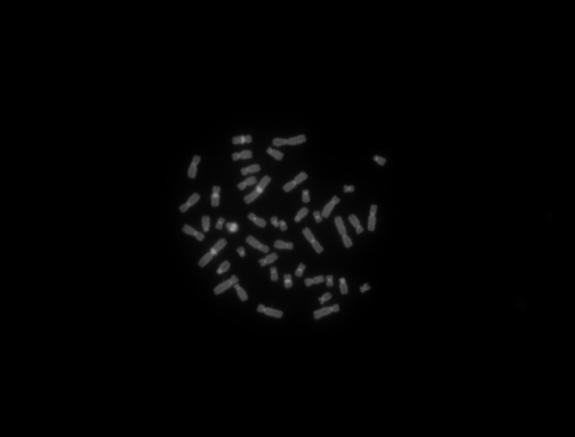

熒光圖像:

熒光C帶2

Y微缺失DAPI藍(lán)紫